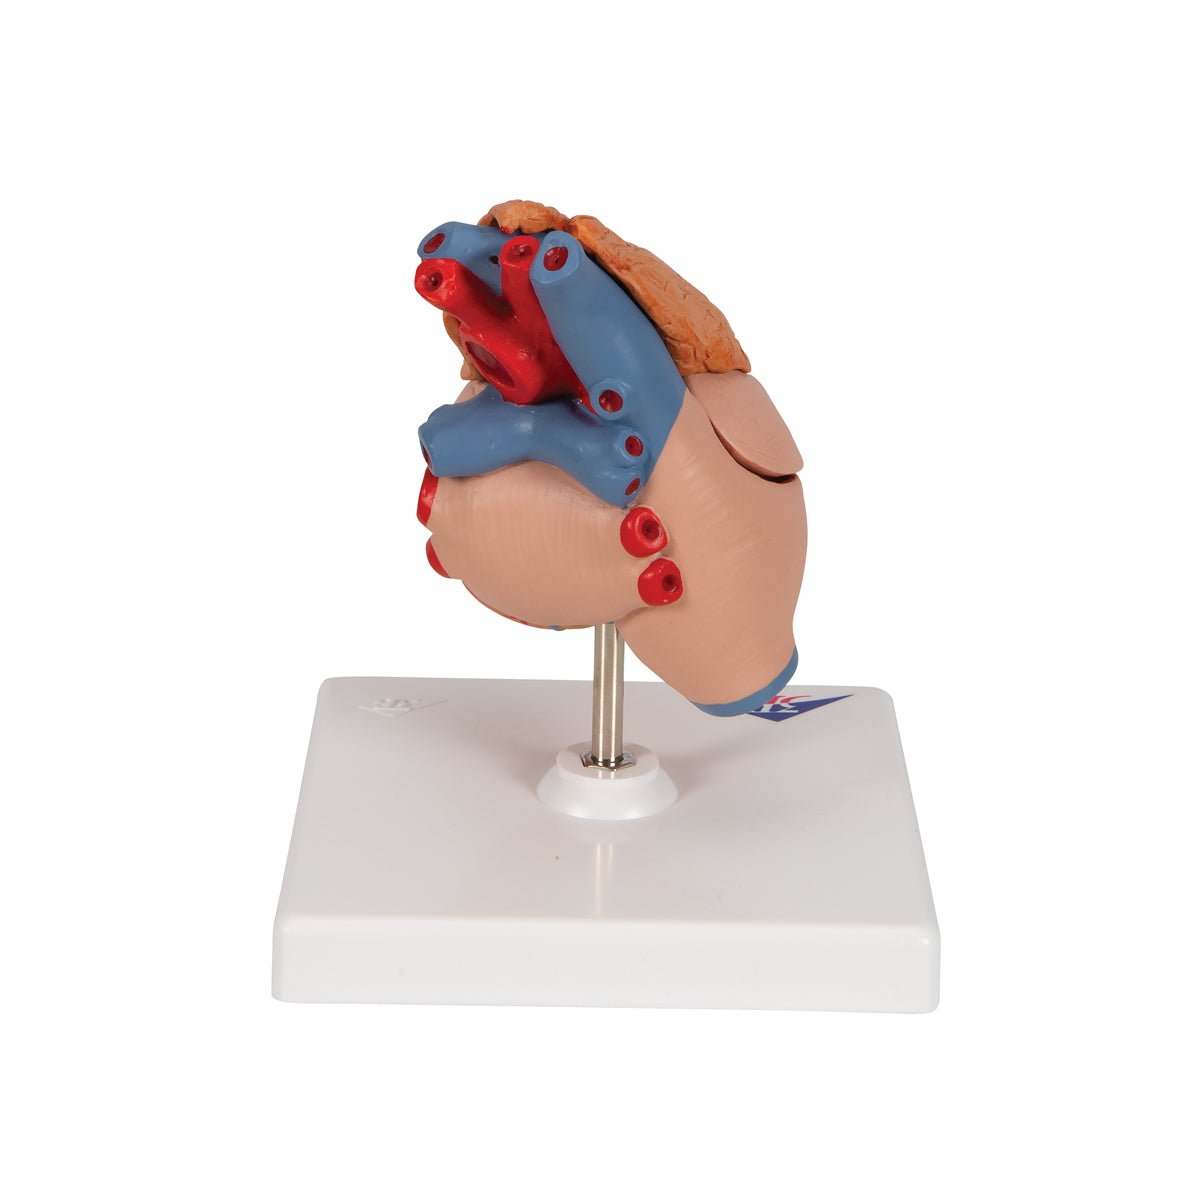

Anatomical models

Selling anatomical models is the mainstay of eAnatomi, although we also spend a lot of resources developing our own anatomical materials such as posters. Anatomical models are used for various purposes and can show both defined tissues, organs and organ systems. Are you looking for a simple model of bone tissue or perhaps an advanced torso model based on MRI technology, you can find it all at eanatomi.com.